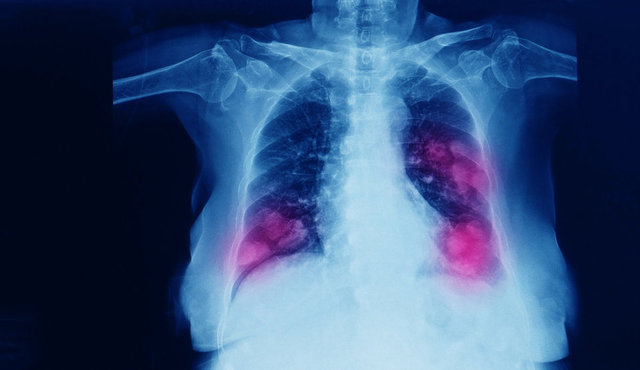

TANI KONULDUĞUNDA ÇOK GEÇ OLABİLİR

Akciğer kanserinin genellikle ileri evrede belirti verdiğini söyleyen Prof. Dr. Görgüner, "En belirgin belirtisi karakter değiştiren öksürüktür. Bunu nefes darlığı, göğüs ağrısı ve kanlı balgam takip eder. İleri evrelerde ses kısıklığı, boyunda ve yüzde şişlik, omuz ağrısı, kolda güçsüzlük, yaygın vücut ağrıları görülebilir. Horner sendromu olarak adlandırılan göz kapağında düşme, göz bebeğinde küçülme ve aynı tarafta yüzün yarısında terleme bozukluğu belirtiler arasındadır. Tanısı konmuş hastaların yüzde 30´unda akciğerde su toplaması meydana gelmektedir. Ayrıca iştahsızlık, kilo kaybı, yorgunluk gibi diğer birçok kanser türünde görülebilen belirtiler de akciğer kanserinde yer alabilir.

Bu belirtilerden herhangi birinin yaşanması durumunda mutlaka bir göğüs hastalıkları bölümüne başvurulmalıdır. Çünkü akciğer kanseri sinsi bir hastalıktır ve genellikle geç belirti verir. Bu durum hastalığın erken tespit edilme olasılığını azaltır ve dolayısıyla tedavi şansını düşürür. Bu nedenle belirli risk faktörlerine sahip kişiler mutlaka düzenli tıbbi kontrollerini yaptırmalı ve belirtileri ciddiye almalıdır" dedi.